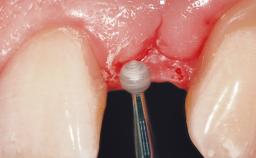

Late Flapless Placement of an Implant in a Maxillary Left Central Incisor Site

A 39-year-old male patient presented with a chief complaint of discomfort and gingival discoloration around his maxillary left central incisor. He was in good general health and was a non-smoker. His past dental history was significant because of the traumatic fracture of tooth 21 in a sporting accident at age 13. Initial dental treatment included endodontic therapy and a full-coverage restoration. The patient became symptomatic 5 years later, when structural failure of the tooth resulted in the dislodgment of the crown. Endodontic retreatment, apical surgery, and post-and-core restoration were performed.

Bone Augmentation Horizontal|Staged

Augmentation Materials Xenogenous|Membrane